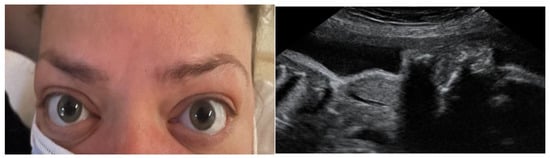

3.2.1. Epidemiology/Definition/Diagnostics